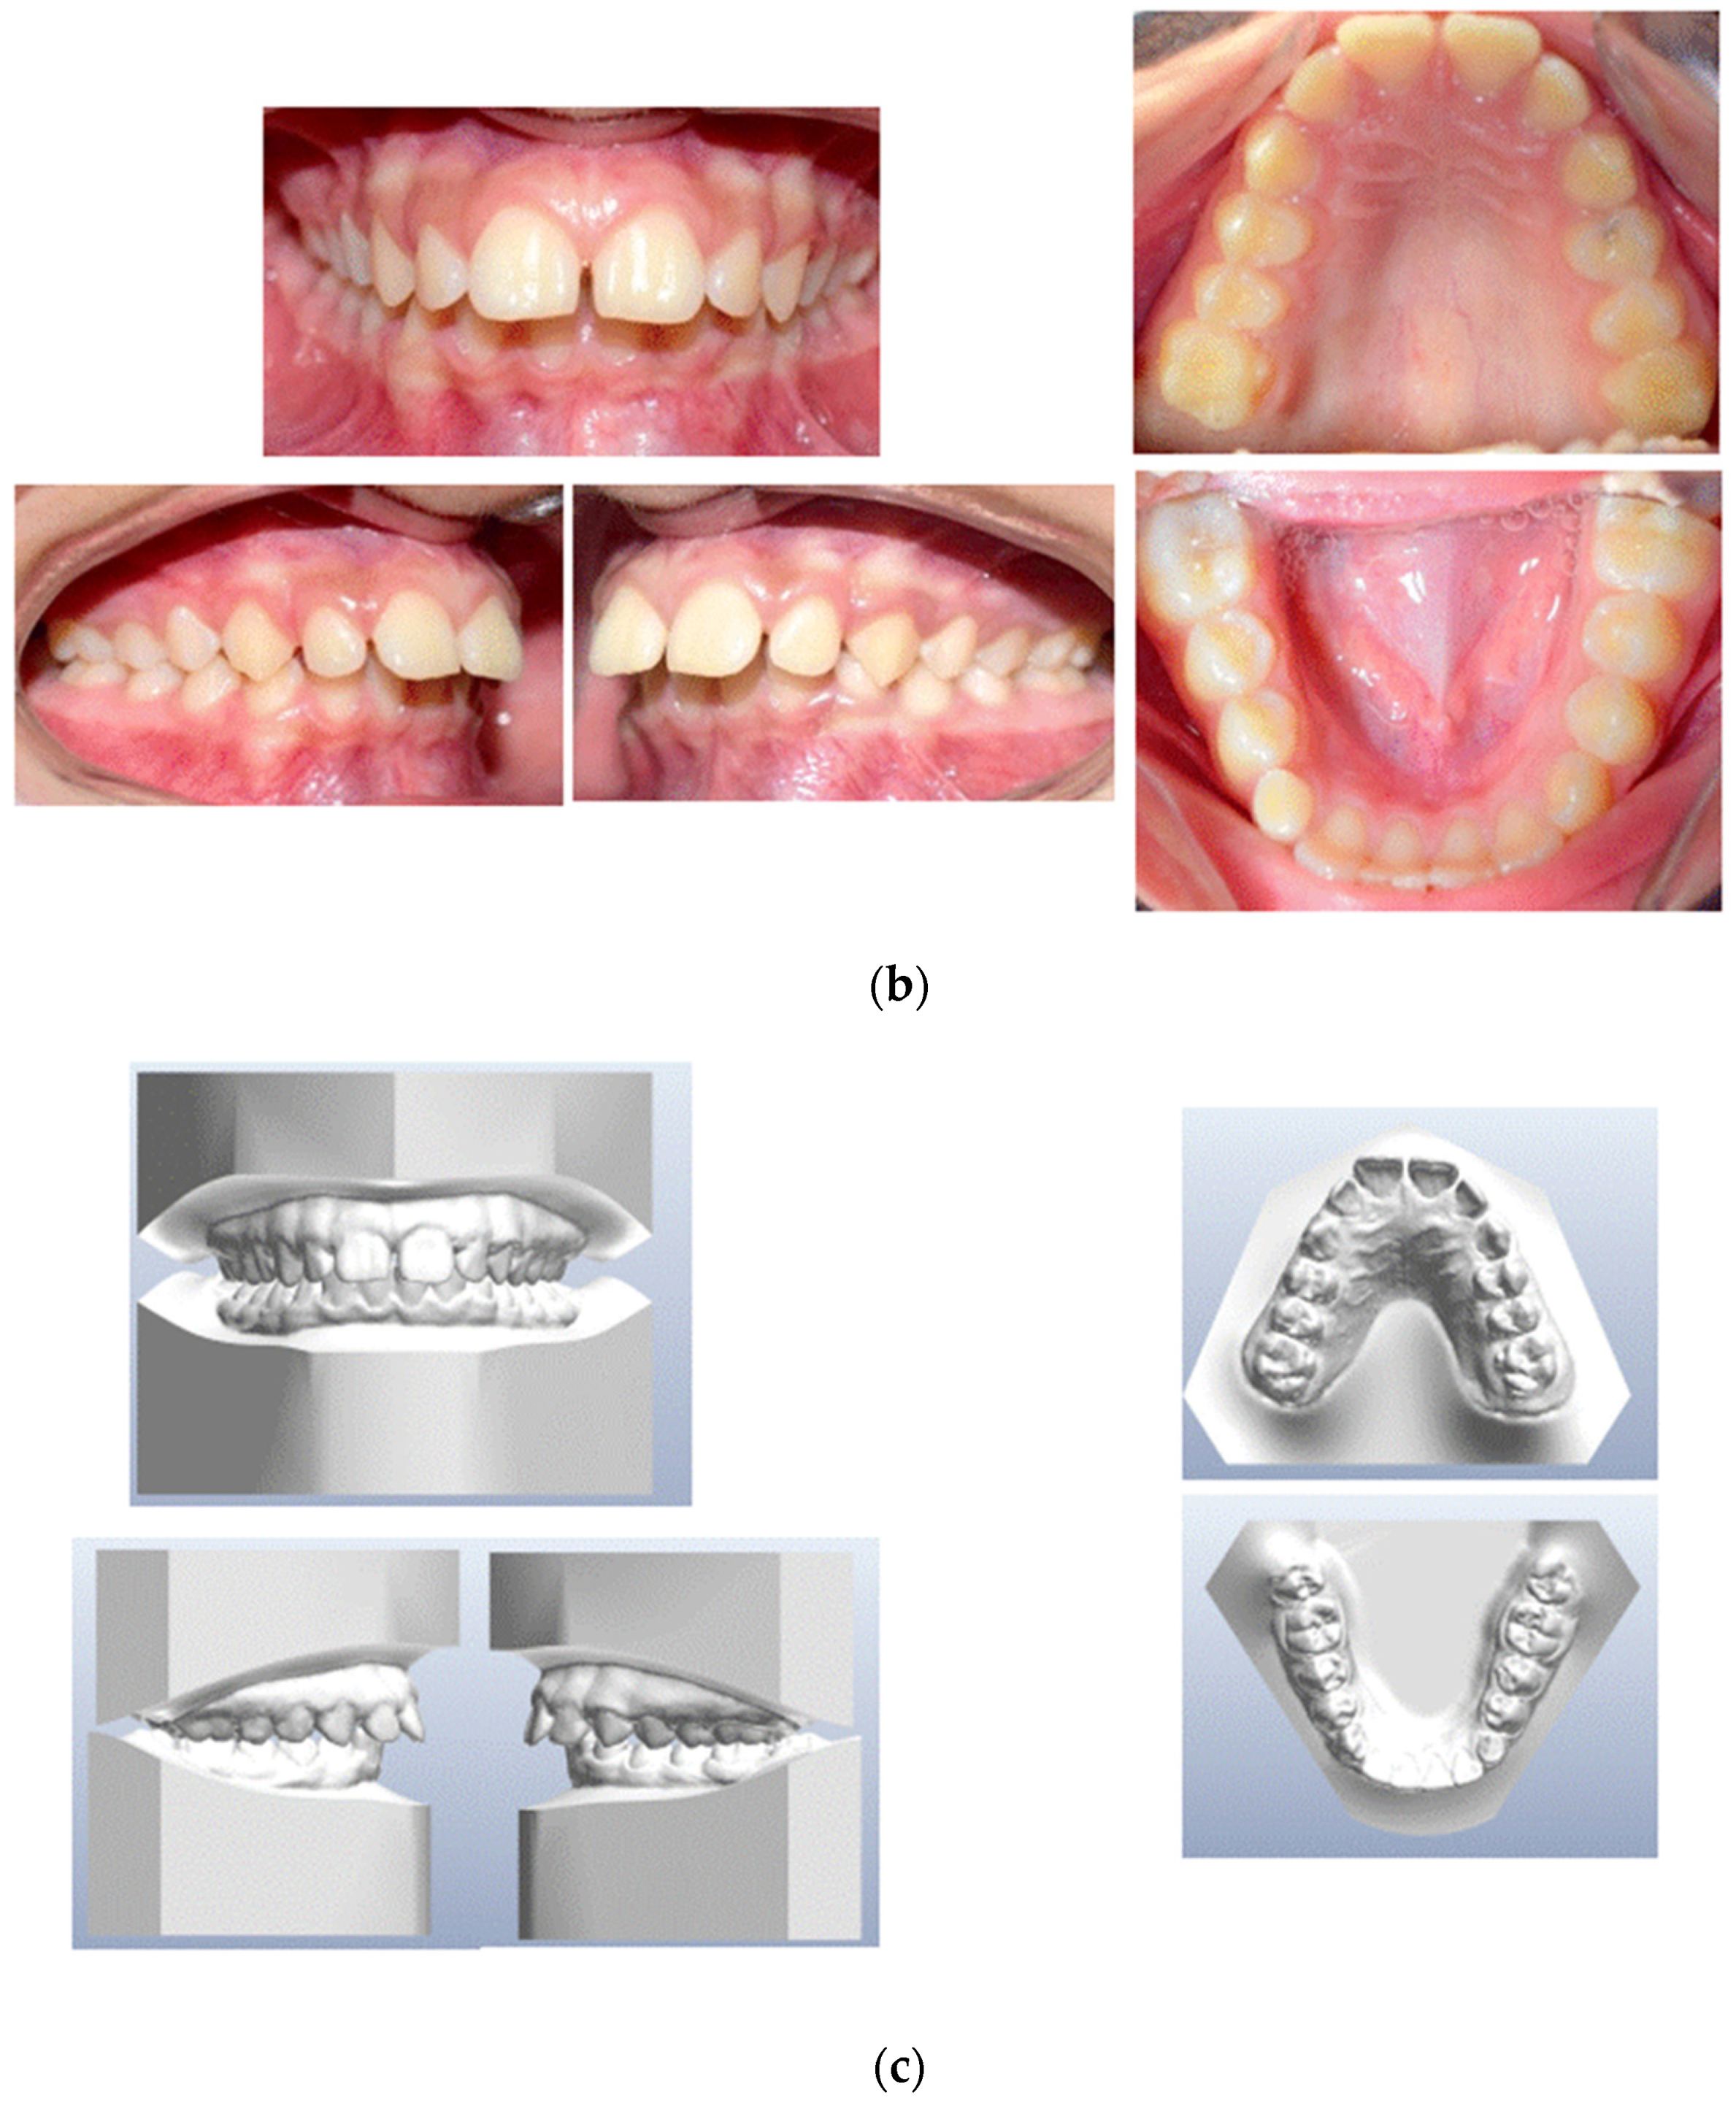

2. Presentation of Case Report

2.1. Treatment Objectives

- Improve overjet and overbite;

- Achieve bilateral canine and molar class I occlusion;

- Increase facial esthetic balance;

- Level the arches and make both coordinate with each other;

- Orthodontic correction of the impacted lower left canine.